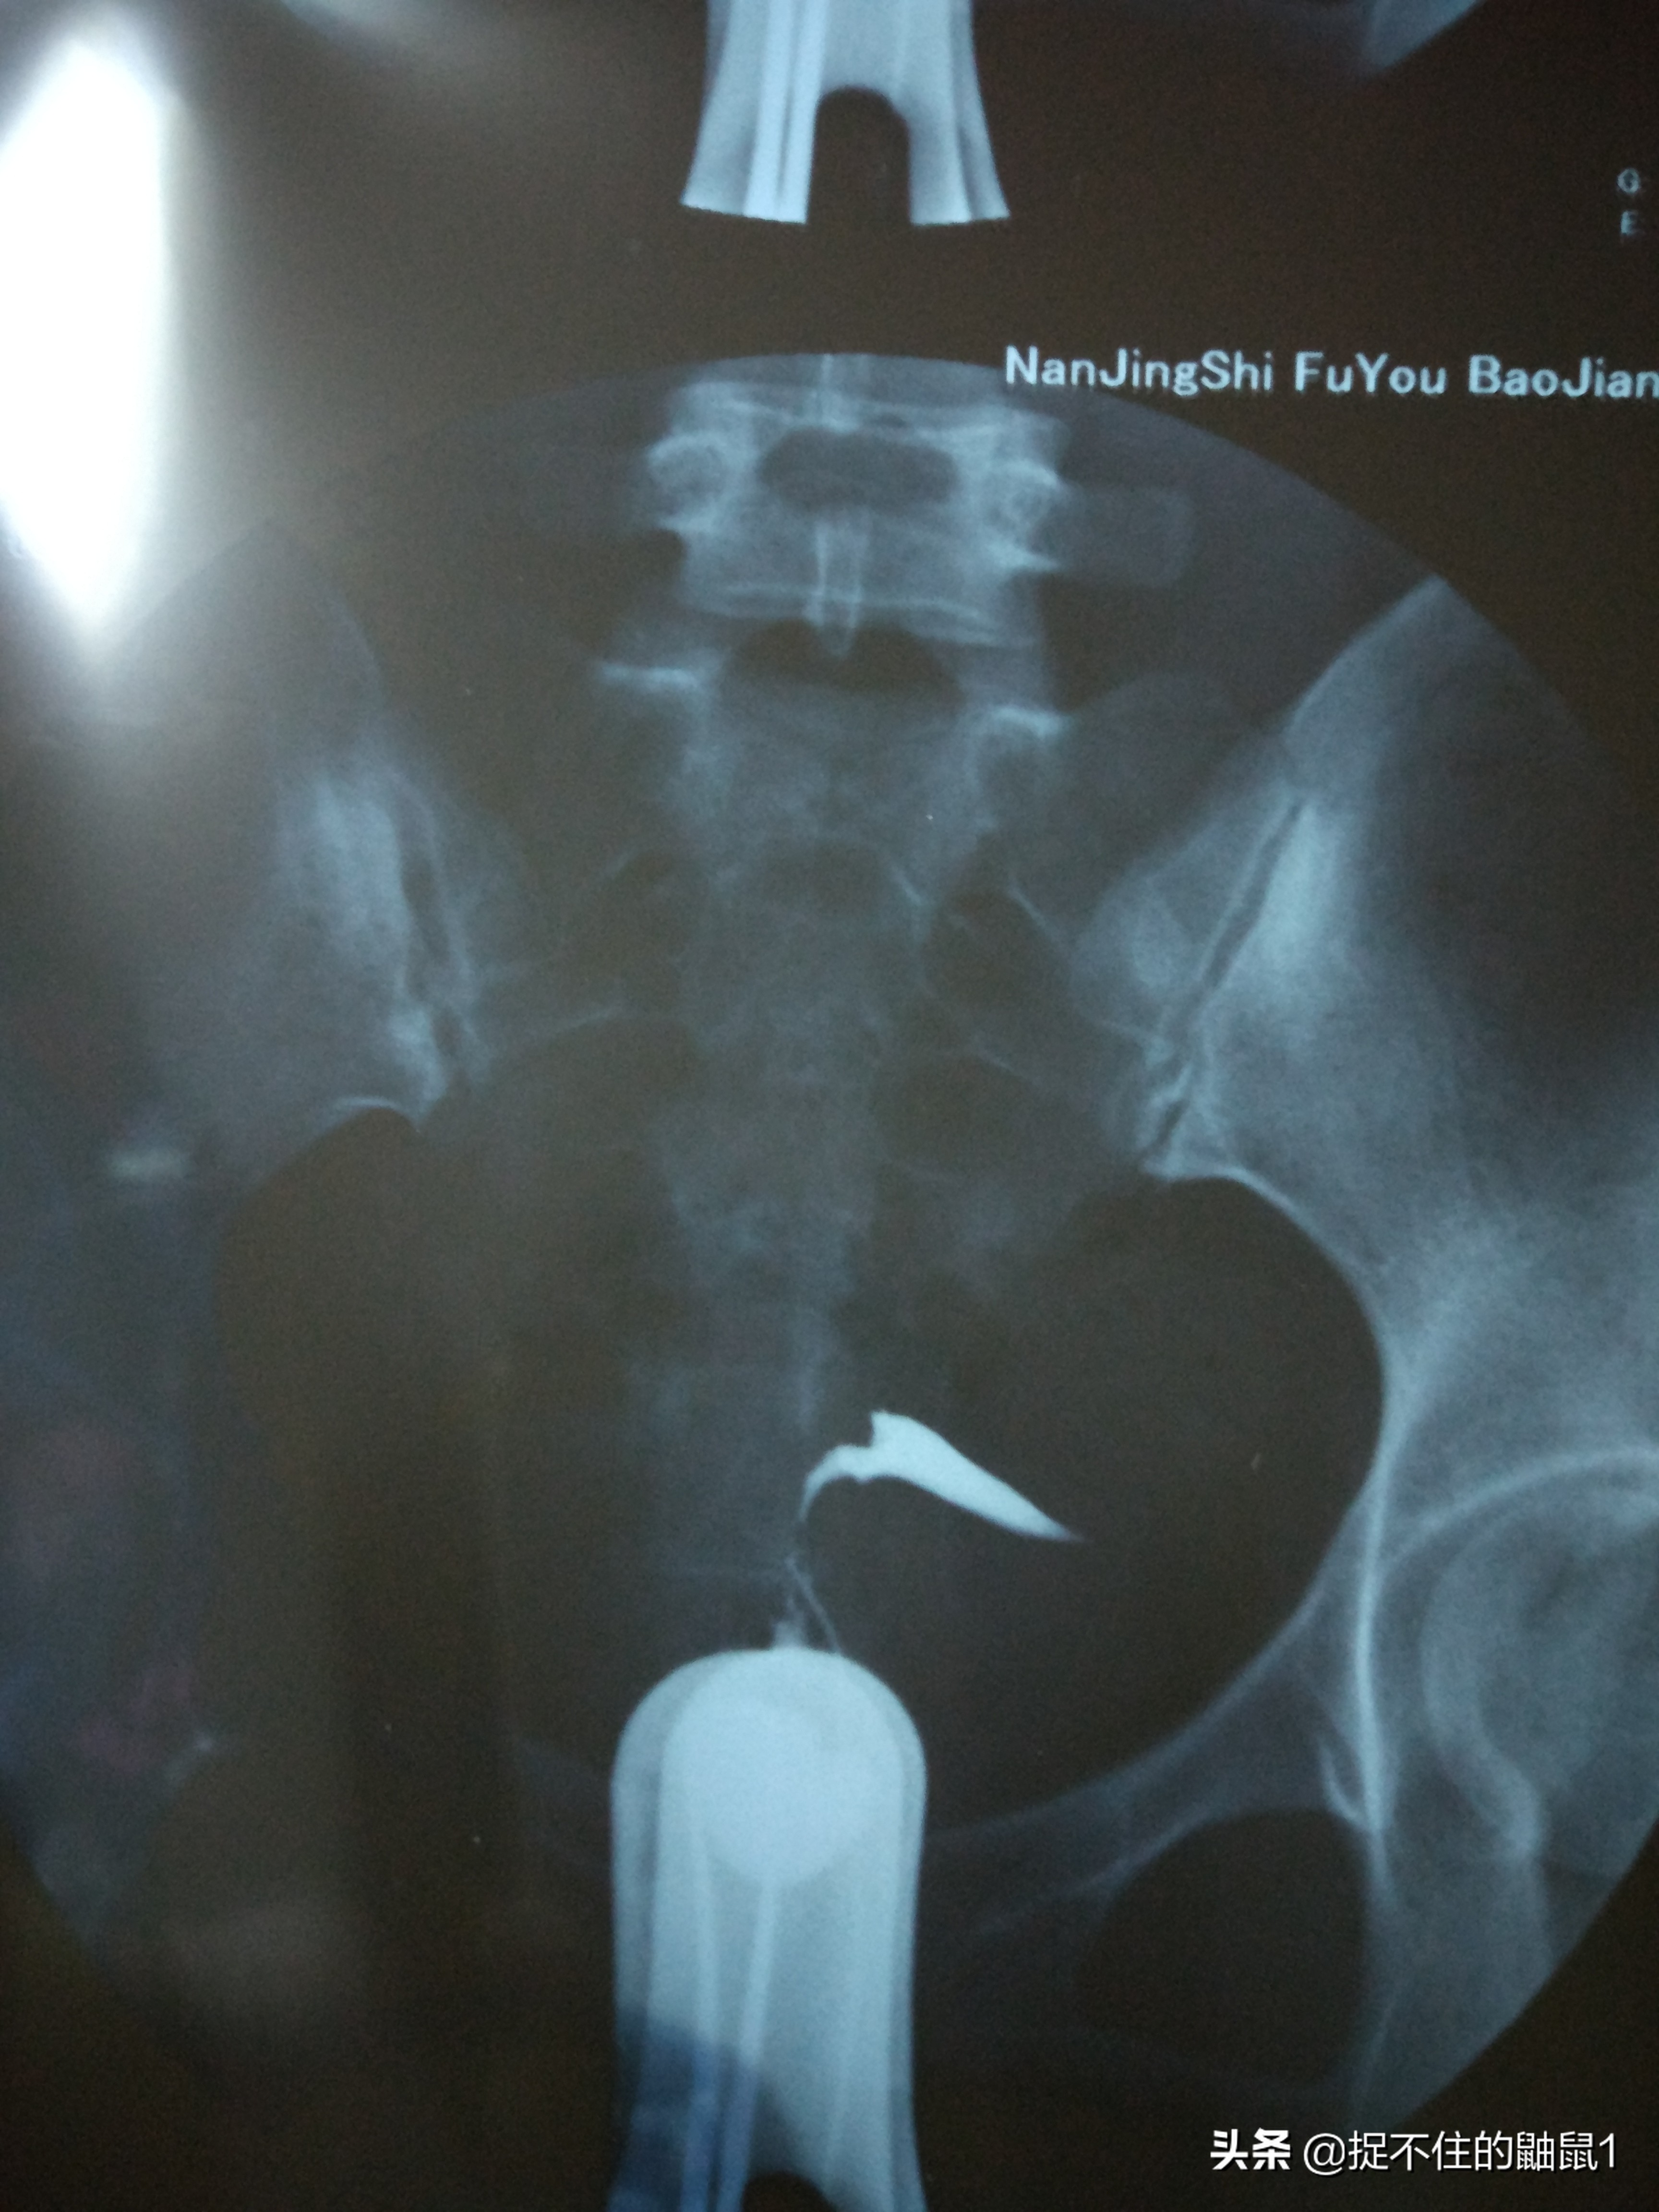

这是诊断书也是我的不育判决书

这是造影片子,发亮的是碘油,这是推入当天的造影